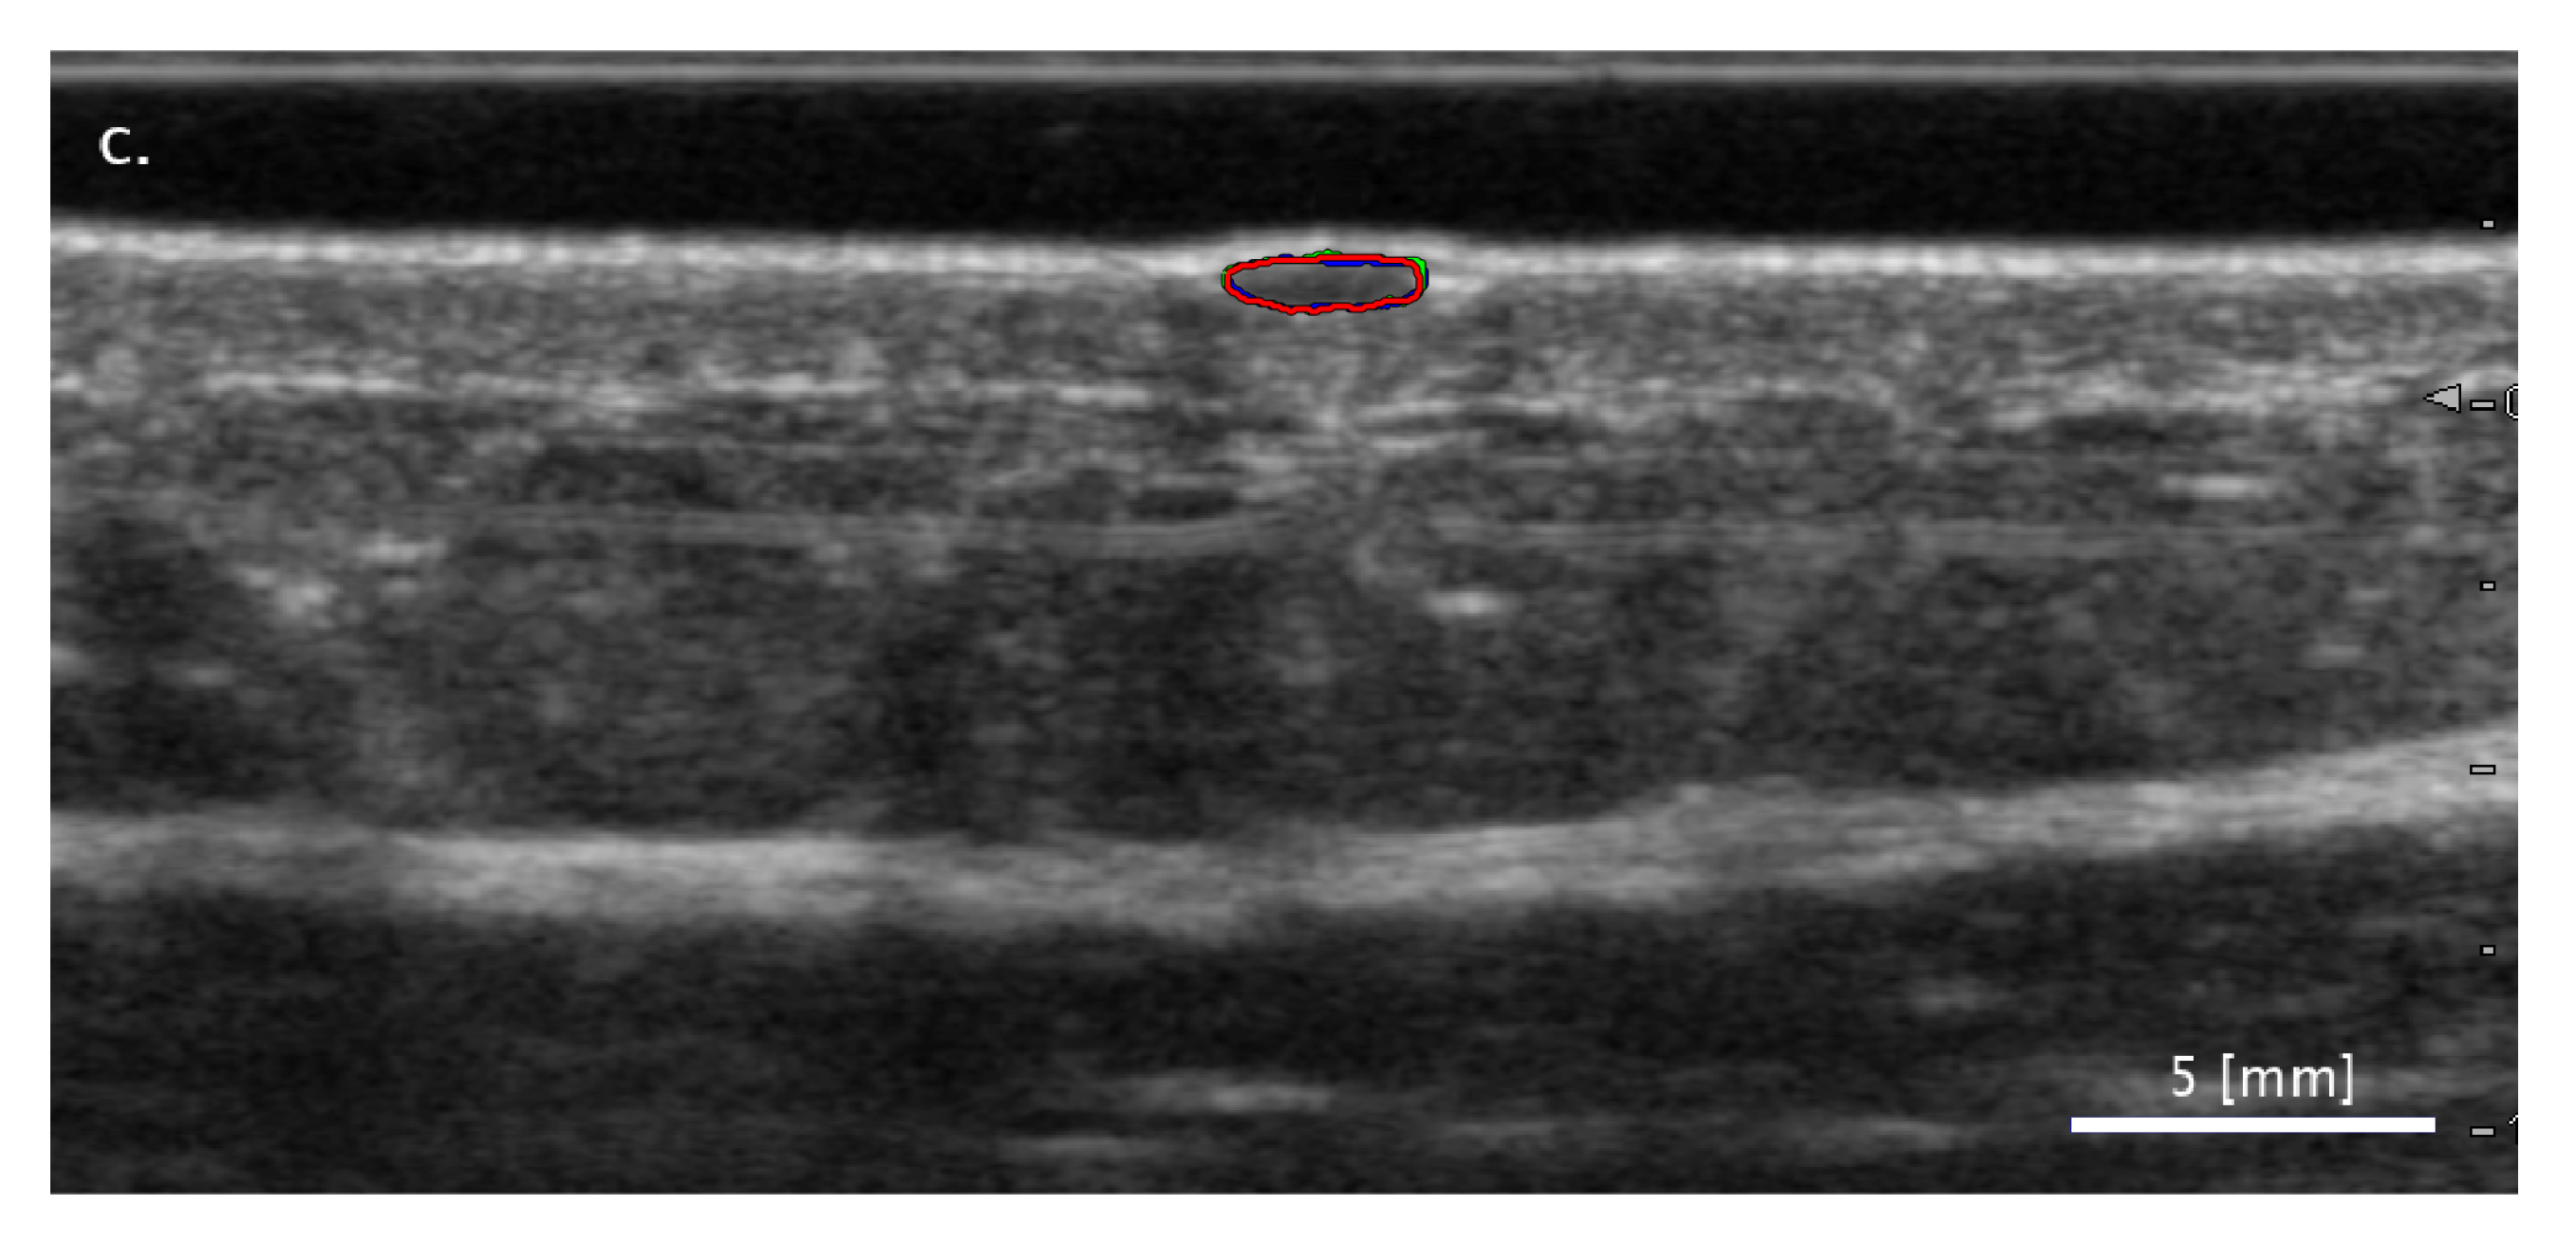

3.2. Comparison of FA and SA Classification Performance with Representative Images

3.2.1. Cases When FA Fails While SA Methods Perform Correctly

3.2.2. Cases When the Two SA Methods Return Different Classifications

3.2.3. Cases When the SA Methods Both Fail While the FA Method Performs Correctly

3.3. Sensitivity of Classification to Changes in Lesion Segmentation